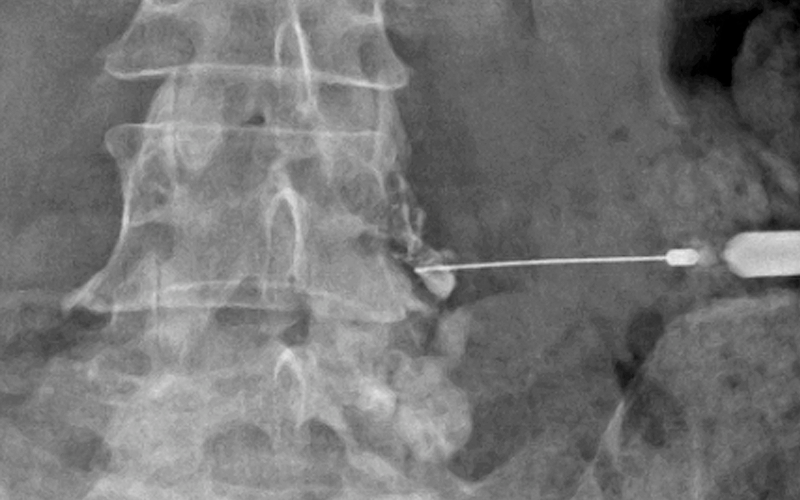

연세BH의원은 개인별 증상과 X-ray 검사를 바탕으로,

실시간 혈관영상 유도 하에 통증 유발 부위(디스크 주변·신경주위·후관절 등)에

특화된 줄기세포 시술을 진행합니다.